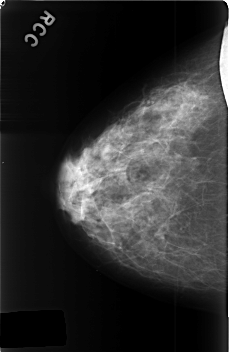

C_0468_1.RIGHT_CC

RIGHT_CC LINES 4576 PIXELS_PER_LINE 2984 BITS_PER_PIXEL 12 RESOLUTION 50 NON_OVERLAY